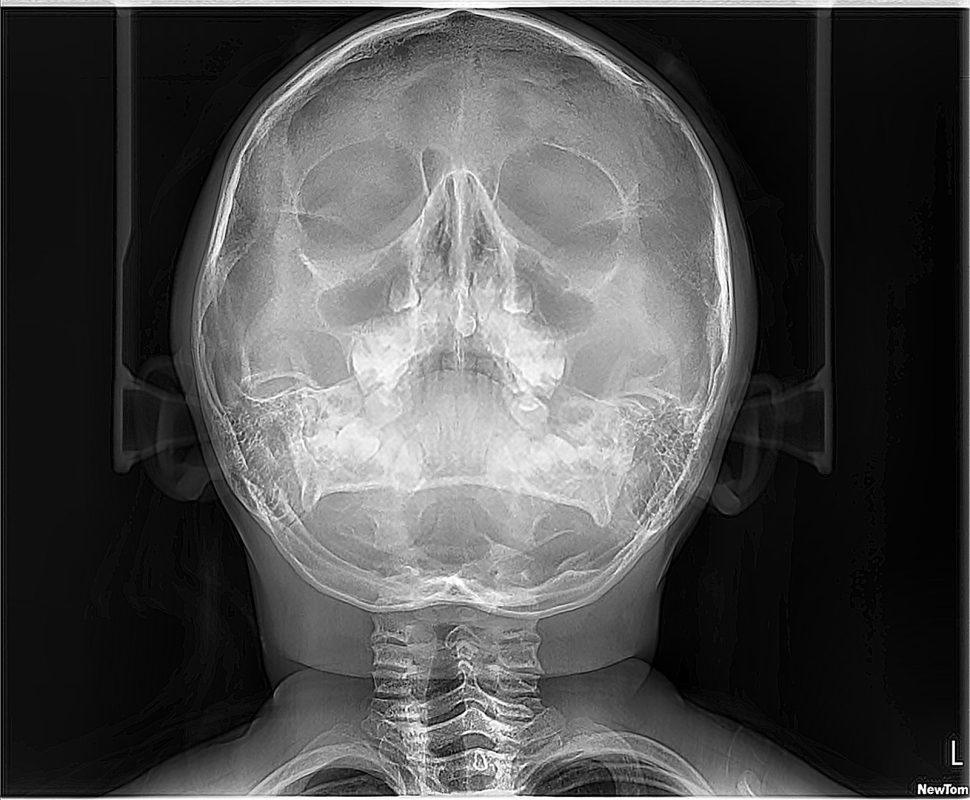

RX SENOS PARANASALES

La radiografía de senos paranasales es una técnica de imagen que se utiliza para examinar las cavidades llenas de aire en los huesos que rodean la nariz, conocidas como senos paranasales. Incluyen los senos maxilares, etmoidales, esfenoidales y frontales. Puede ser realizada para diversos propósitos, como:

CADWELL, CAVUM, WATERS